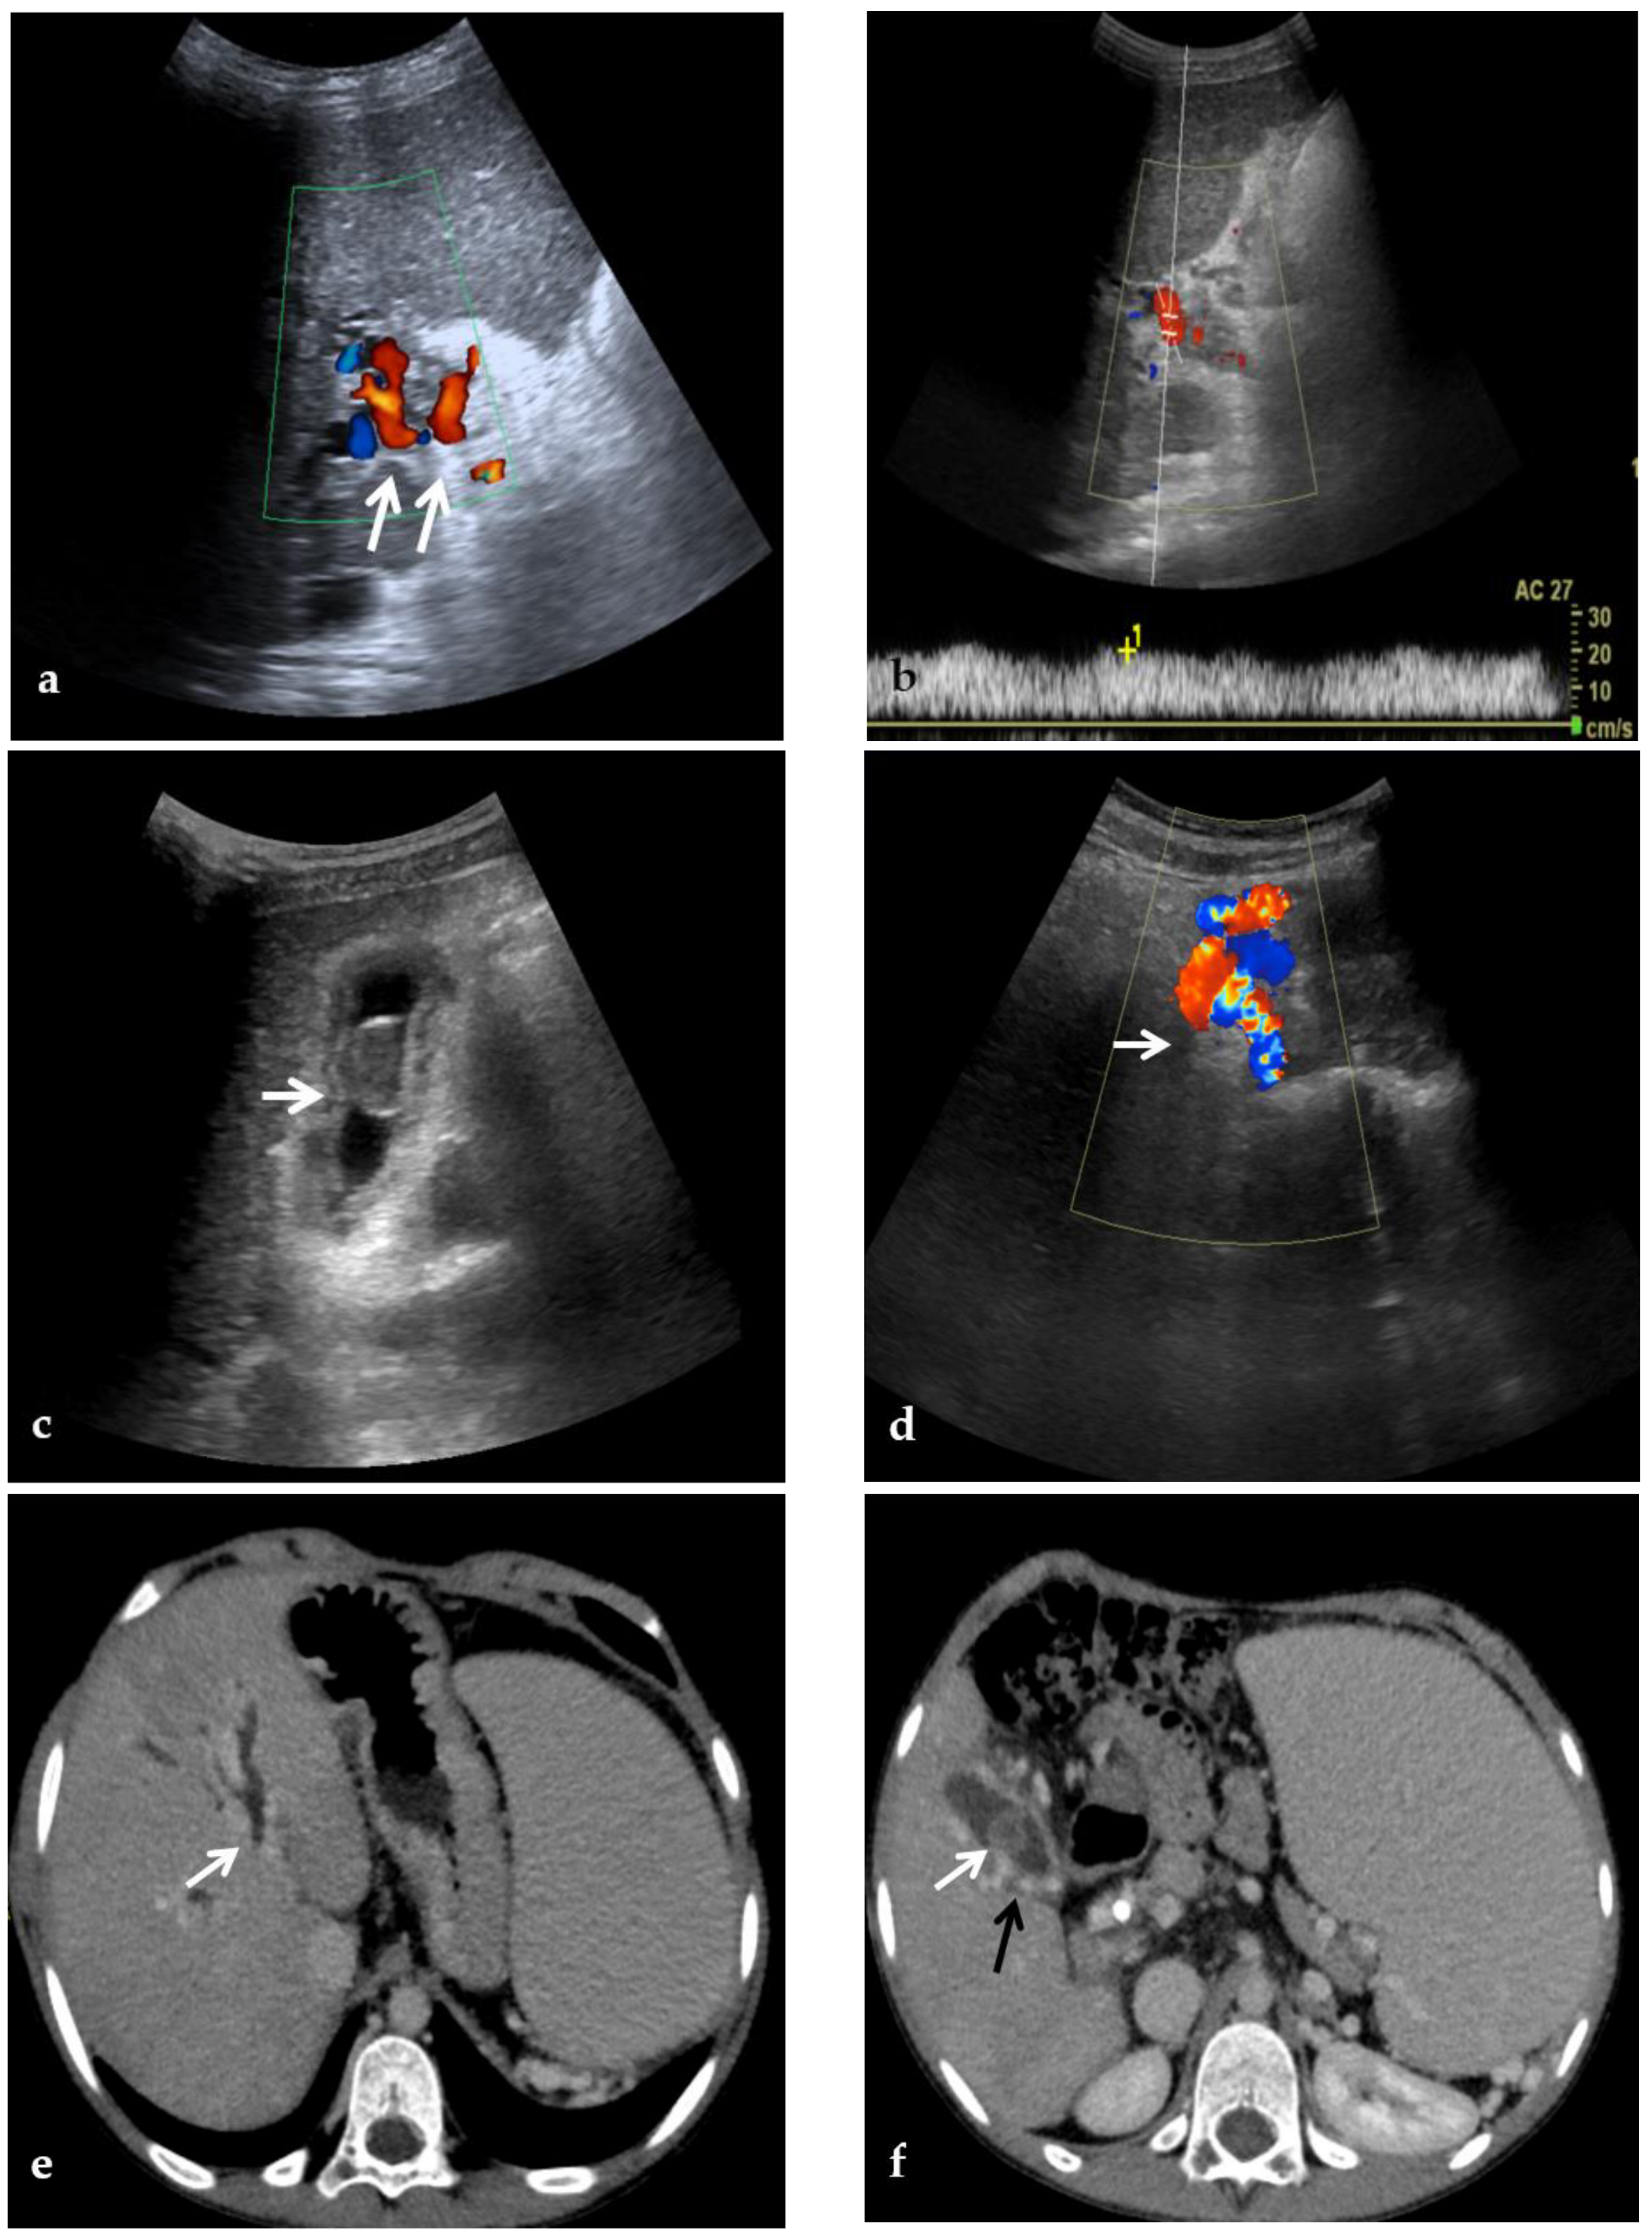

3.3.2. Portal Biliopathy

Portal biliopathy is defined as the presence of abnormalities of the extrahepatic and intrahepatic bile ducts and gallbladder walls in patients with noncirrhotic/non-neoplastic PVT [2] (Figure 2).

CDUS, CT, and MR images of a 9-year-old male with intrahepatic and extrahepatic cavernous transformation of the portal vein and portal biliopathy who presented with jaundice and cholangitis. (a) A Color-Doppler Ultrasound image shows multiple collateral vessels at the porta hepatis (arrows) and the absence of the main portal trunk. (b) Spectral evaluation of the major collateral vein of the cavernoma shows an hepatopetal flow with a velocity within normal ranges, which could potentially be misleading by an unexperienced operator. (c) An ultrasound image scan through the gallbladder shows a mildly echogenic endoluminal stone in the gallbladder (arrow). (d) Color-Doppler Ultrasound image shows multiple dilated collateral cavernous vessels in the gallbladder fossa (arrow). (e) Portal phase axial CT image shows dilation of intrahepatic biliary ducts (arrow) due to extrinsic compression of the common biliary duct by the cavernoma. (f) A caudal axial CT view in the portal venous phase shows a mildly hyperdense stone in the gallbladder (white arrow) which is surrounded by dilated cavernous vessels (black arrow). (g) Axial T2-weighted MR image shows intrahepatic biliary dilatation (arrows) due to common biliary duct extrinsic obstruction by prominent paracholedochal collateral cavernous vessels. (h) A caudal axial T2-weighted MR view shows wall thickening of the gallbladder (white arrows) which contains other multiple small gallstones in the fundus (black arrow).

Although radiologic manifestations of portal cavernoma biliary damage are described in up to 100% of patients with extrahepatic PVT, most of them are initially asymptomatic. In one study [43], only 1 of 20 patients had choledocholithiasis, whereas, in another study [44], biliary changes were associated mainly with biochemical abnormalities.

However, progressive portal cavernoma cholangiopathy may become symptomatic in 5% to 38% of patients presenting with jaundice, pain, recurrent cholangitis, and cholecystitis, typically 8–10 years after diagnosis, and leads to severe complications, including secondary biliary cirrhosis in the case of prolonged bile duct obstruction [45,46].

Biliary abnormalities are common in PVT because paracholedochal and paracholecystic veins form the portoportal collaterals to bypass the obstructed segment of the portal vein. Biliary abnormalities may be explained either by compression of bile ducts by prominent paracholedochal and epicholedochal collateral vessels (indentations and wall irregularities) or ischemic injury of the bile ducts as a result of thrombosis of veins draining the bile duct (leading to ischemic stricture development). Biliary stricture is a frequent finding on MR examinations in the setting of portal cavernoma biliopathy, affecting up to 93.7% of patients [47].

The ultrasonographic diagnosis of PVT relies on the presence of echogenic material obstructing the lumen of the vessel and the complete or partial absence of flow in the portal vein at color flow Doppler imaging [51] (Figure 3). As the chronic thrombus ages and calcifies, CDUS may show areas of increased echogenicity. In addition, the collateral veins from cavernous transformation around the segments of PVT display a serpiginous mixed-color pattern on CDUS and are anechoic on gray-scale imaging [39,52]. The appearance of the portal cavernoma has been described as a “spongelike mass”, a distinctive tangle of tortuous vessels in the porta hepatis characterized by hepatopetal flow with loss of normal portal phasicity [2] (Figure 2). However, discriminating cavernous collaterals from the portal vein in children with PVT can be very difficult.

In portal biliopathy CDUS provides additional information regarding the presence of gallbladder varices, observed in about 35% of patients. Gallbladder varices appear as tortuous, dilated vessels in or around the wall of the gallbladder or in the gallbladder fossa. Moreover, ultrasound can detect the presence of cholelithiasis caused by biliary obstruction secondary to portal biliopathy: gallstones are characteristically echogenic and demonstrate posterior acoustic shadowing regardless of the gallstone composition [48] (Figure 2).